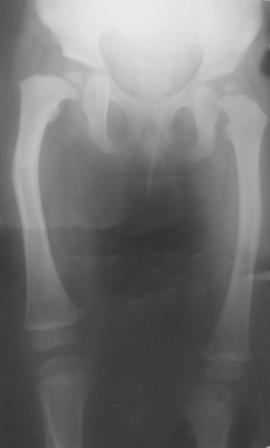

Уважаемые коллеги. Осмотрена девочка 2007г.р. При рождении двухсторонная косолапость, двухсторонный врожденный вывых бедер, лечилась консервативно.

В данное время ходит самостоятельно, прихрамывает на прав.ногу, прав. нога укорочена на 3,5см и и находится в положении внутренней ротации 40гр. Леч.врач зав. кафедрой Т.О.мед. института.

Планируется подвертельная деротационно-вальгизирущая остеотомия бедра. Или остеотомия на верщине деформации бедра с удлинением по методу Илизарова.

Добрый день, уважаемый Абдурашид. Начнем с тазобедренных суставов. Какая количественная характеристика параметров этих суставов?Я имею в виду угол антеверзии и шеечно-диафизарный угол, углы горизонтального и вертикального соответствия? Судя по рентгенограмме, у больного в первую очередь весьма проблемен левый тазобедренный сустав, который находится в положении подвывиха!Нога находится в положении внутренней ротации-куда смотрит коленный сустав?Одной из проблем лечения косолапости является торсия костей голени!! При этом стопа смотрит внутрь, но ось коленного сустава нормальна! Если имеет место торсия костей голени, то после остеотомии вы получите коленный сустав, плоскость движений которого будет смещена наружу на величину деротации

Простые расчеты на представленных Вами электронном изображении показывают, что анатомическая разница длины бедер составляет примерно 3.7%,те же цифры получаются и при измерении относительной разницы.

Следовательно , чтобы получить дефицит 3.5 см. необходимо иметь исходную почти метровую длину бедер.

Возможно ошибку в измерении провоцирует не устраненные деформации стоп,которые и являются в данном клиническом случае ведущими.Попробуйте начать с коррекции деформации стоп, а потом вернетесь к оценке состояния т.б суставов и бедер.